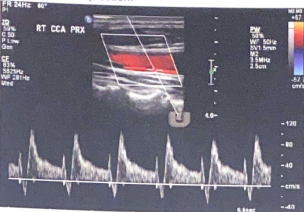

Patient admitted with sudden onset of LT sided weakness and aphasia x 48 hours. Carotid duplex ordered and you obtain this image of RT ICA.

1. Considering patient symptoms, is this a TIA? Why or why not?

2. Considering velocities, what does this image indicate?

3. Describe waveform down stream from this current location.

No because its more than 24 hours

That there is a hemodynamically significant stenosis because the velocities are pretty high at 367.3 cm/s

would be a tardus parvus waveform (slow rise, slow fall)